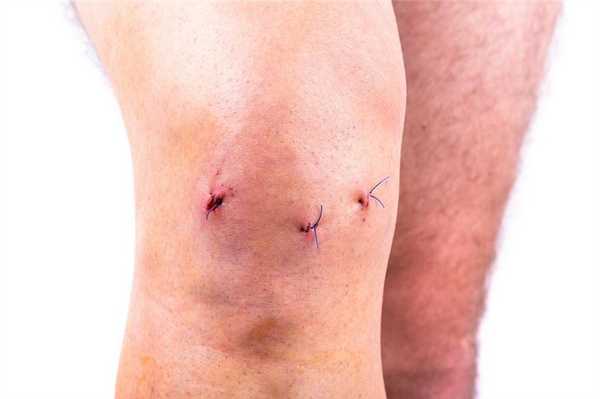

Операционные раны после артроскопии коленного сустава.

Швы на колене после операции снимают обычно на 10 сутки. За это время должно произойти окончательное сращение краев раны, зафиксированных хирургическими нитями. Если разрез незначительный и быстро зажил, вам снимут швы на 7-й день. Вообще способность к регенерации мягких тканей, которые были рассечены в момент операции, у всех людей разная. У пожилой категории пациентов или людей, страдающих диабетом, окончательное заживление может состояться только на 12-14 день.

Судя по шрамам у данного пациента не левом коленном суставе была проведена частичная замена и артроскопия. Швы выглядят хорошо.